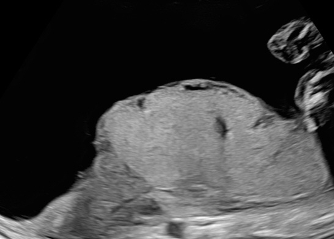

La TAPS è una complicanza conseguente ad uno squilibrio emodinamico tra gemelli identici che condividono una sola placenta (monocoriali). Un gemello, definito donatore, sviluppa anemia (ovvero riduzione della quantità di globuli rossi), mentre l’altro gemello, definito ricevente, sviluppa policitemia (eccesso di globuli rossi con aumento della viscosità del sangue).Senza trattamento, possono comparire complicanze talora mortali in uno o entrambi i gemelli.

Il trattamento mediante lasercoagulazione delle anastomosi placentari in fetoscopia è l’unica opzione con cui si tratta la causa della TAPS in utero, perchè si agisce sui vasi in cui avviene lo squilibrio emodinamico tra i gemelli. Esso è il trattamento di elezione per una differente complicanza, la TTTS (twin twin transfusion syndrome), in cui è presente il polidramnios (eccesso di liquido amniotico) in un gemello, che rende agevole l’accesso nella cavità uterina e la visualizzazione della anastomosi placentari; nel caso della TAPS il polidramnios non è presente e pertanto la procedura laser diventa più complicata. Inoltre le anastomosi che sono responsabili della TAPS sono molto piccole e possono essere più difficili da individuare.